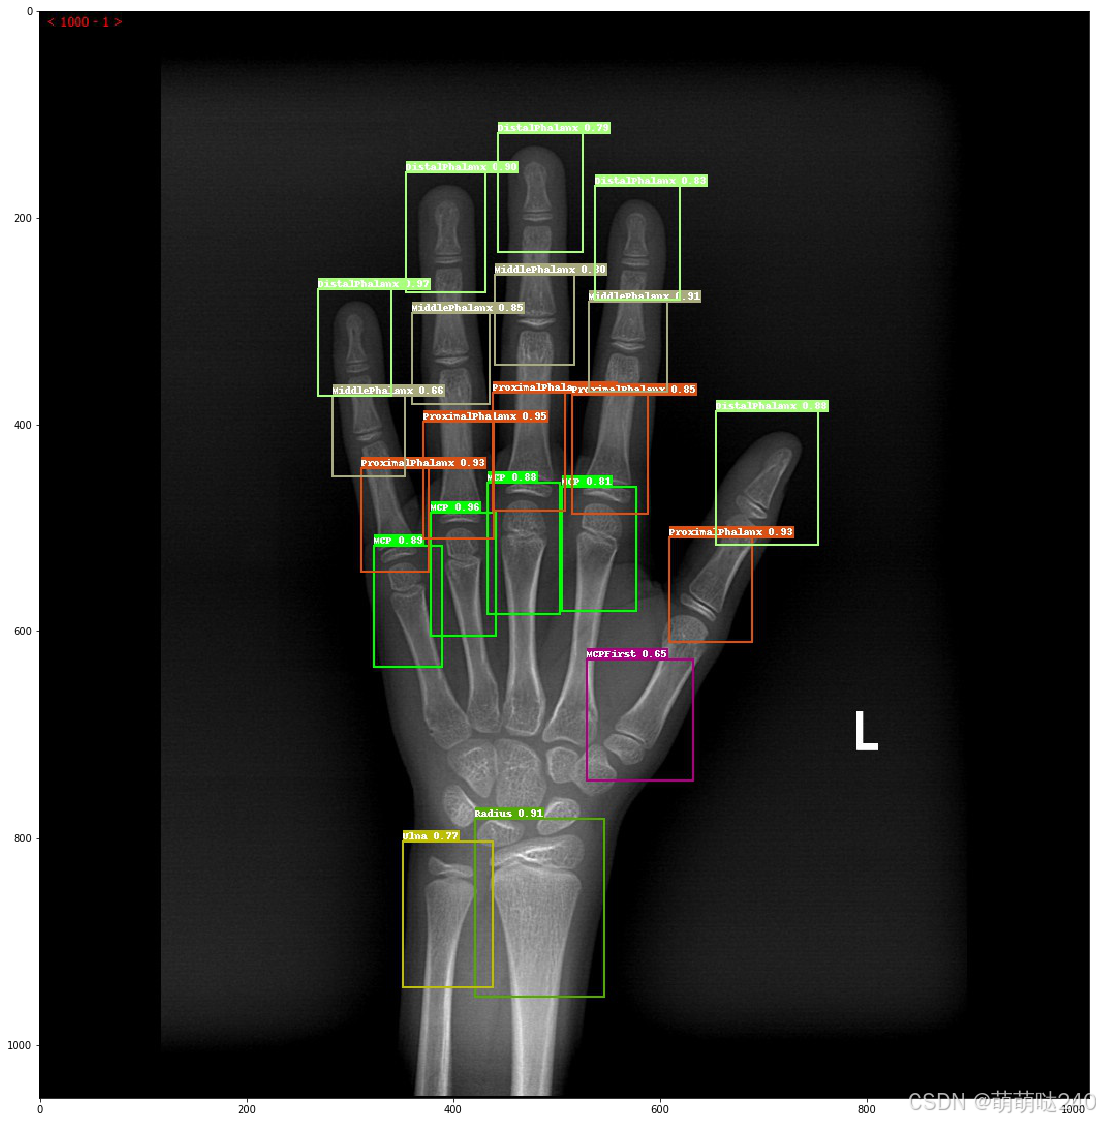

但是发现医生写骨龄的方法。在计算机任务中,好像目标检测 + 分类任务。所有就有这个项目。

训练9个模型

--eval#一键预测

--draw_threshold=0.2#展示预测图片

图一是预测结果,图二是医生诊断结果

虽然训练分类模型的精度不是很高,但是整体效果还是可以。本来临床需要诊断骨龄需要10多分钟,现在缩短到1分钟左右就可以。后续会不断调整数据,增加数据,训练一个更好的模型。后面会压缩模型,结合pyqt部署成桌面应用,会投放到科室给临床使用。这个检测+分类的工作方式,其实还有一个好处,就是临床可以看到每个关节的预测效果,根据临床的需要,可以自行判断关节是否预测准确,给予适当的修正。而不是黑盒子出来一个骨龄数字,直接下诊断。最终还是回归到机器辅助医生下诊断。